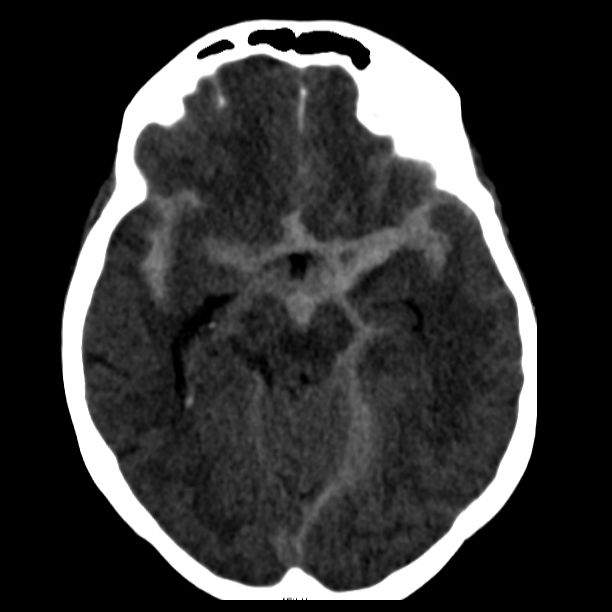

Angiographische Darstellung einer AVM

Angiographische Darstellung einer AVM vor dem Therapiebeginn (links), nach erfolgreicher Teilembolisation (Mitte) und nach vollständiger mikrochirurgischer Resektion (rechts)